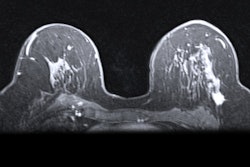

It is a commonly held belief among radiologists that breast density has a key role in the breast cancer screening process. Studies show that women with very dense breasts are four to five times more likely to develop breast cancer than women with less dense breasts.1,2 Screening for cancer is especially important for women with dense breasts, yet unfortunately, it can also be particularly challenging. Underlying cancers can be masked by dense breast tissue on 2D mammograms and, therefore, extremely hard to find

Currently, our team is assessing breast density, looking at the digital images and assigning density based on the ACR's BI-RADS categories. Although this technique has demonstrated good results for many patients over the years, visual assessment is not always reproducible with different intra- and interreader agreement, which means there is room for argument in how to classify a given patient. Standardizing these assessments with quantitative methods is fundamental to introduce breast density as a risk assessment method.

Our department has recently received approval to start a risk-based breast screening study that will follow up to 10,000 45-year-old women over five years. These patients' mammographic densities will be interpreted by two radiologists using the ACR's BI-RADS visual method and also software that will calculate the breast density based on quantitative density measurements. Evaluation of patients' breast density may provide information on their potential breast cancer risk, and it also could lead to establishing the best personalized screening for them.

Previous studies have shown that patients with dense breasts have optional screening choices to increase their cancer detection rate. In 2017, the results of the Verona pilot study showed that digital breast tomosynthesis (DBT) identified more cancers in dense breasts compared with full-field digital mammography (FFDM) (12.9 x 1,000 versus 4.5 x 1,000 in BI-RADS C-D).4

Although ultrasound and MRI options also are beneficial for cancer detection in dense breasts, when patients are screened with DBT and their mammograms come back normal, they can rest assured that they do not need further follow-up. With a uniform approach to prioritize DBT screening for women with dense breasts, clinicians can help increase the chances of early detection for their patients who have breast cancer while also avoiding follow-up for patients who don't.